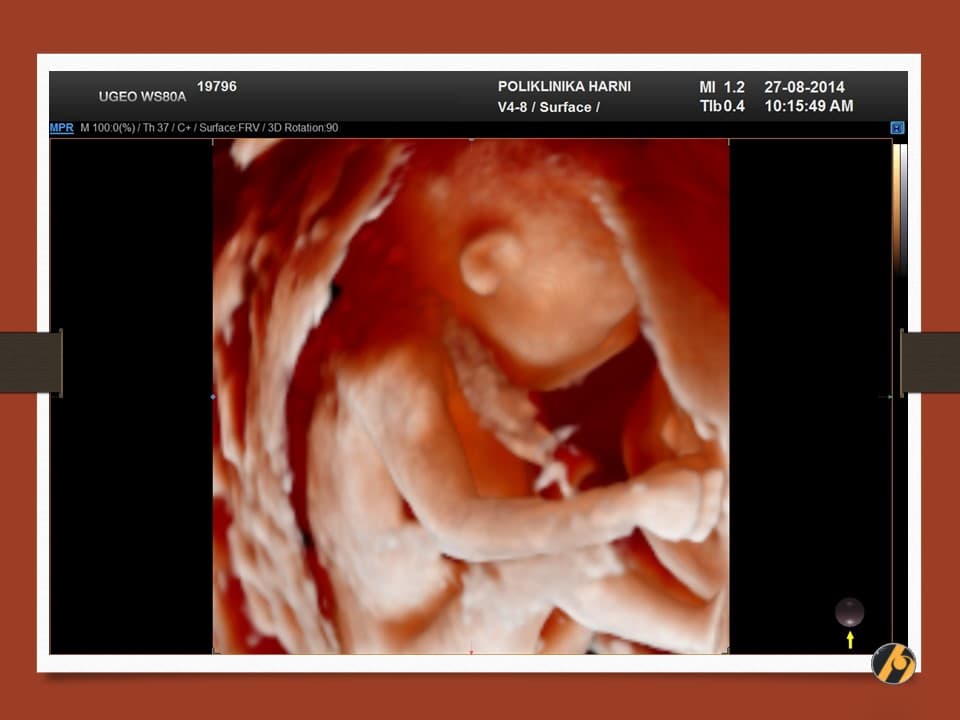

Nastavlja se finiji razvitak kože vaše bebe, koja je u ovo vrijeme tanka i prozirna i kroz koju se vidi mnoštvo krvnih žilica. Lanugo dlačice prekrivaju gotovo cijelu površinu kože bebe, a jasnije se ističu dlačice na obrvama. Počinje rasti kosa na glavi, a pigmentne stanice počinju stvarati crni pigment.

Razvijaju se daljnji centri okoštavanja i kosti, kao i koštana moždina koja preuzima funkciju žumanjčane vreće u stvaranju krvi djeteta. Zglobovi bebe su sve pokretljiviji, a beba s time i sve savitljivija. Sada vaša beba može svoje prstiće stisnuti u šaku.

Vaša beba guta amnijsku tekućinu koja ga okružuje, što pomaže sazrijevanju respiratornog sustava. Bebine oči su i dalje zatvorene, ali beba počinju reagirati na svjetlost izvan vaše maternice. Od ovog tjedna vaše će dijete početi čuti zvukove u vašem tijelu, poput otkucaja srca i trbuha.

Vaša beba dugačka je 10 - 12 cm, a teška 50 - 100 g.